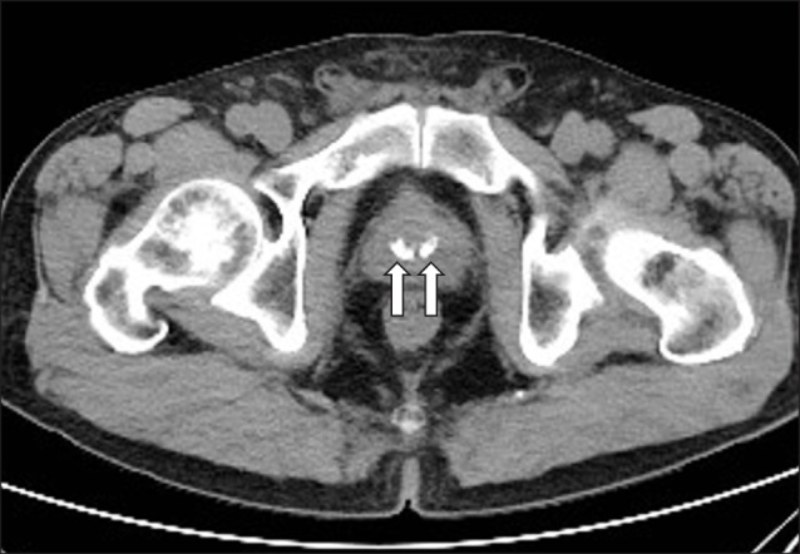

Vôi hóa tuyến tiền liệt thường được phát hiện qua một số phương pháp chẩn đoán sau:

Bác sĩ sẽ đưa một ngón tay đã đeo găng và được bôi trơn vào trực tràng nhằm kiểm trang xung quanh thành trực tràng để tìm dấu hiệu vôi hóa và các bất thường khác.